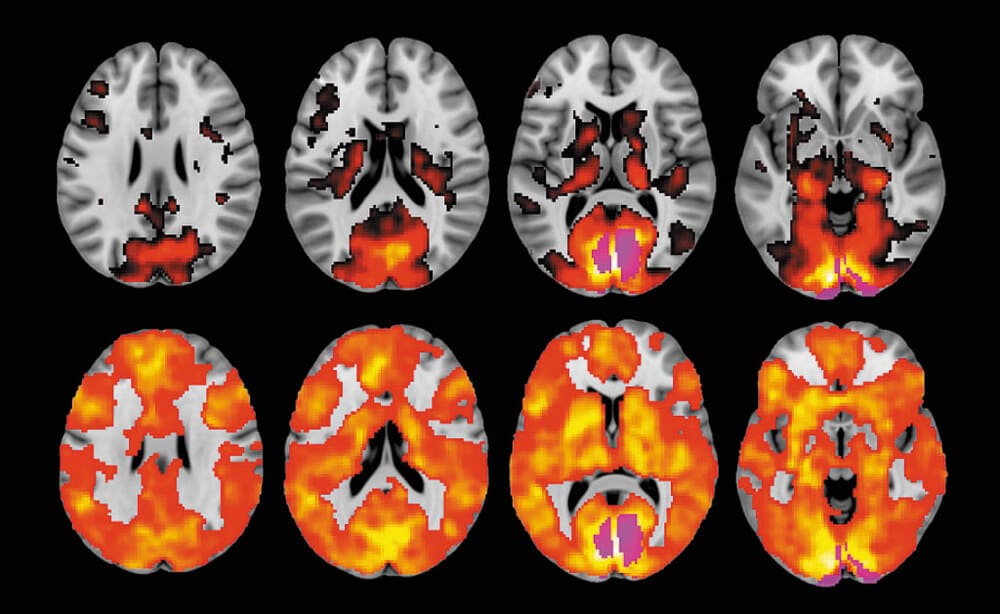

Сіль — це важка наркотична речовина. Вона належить до групи стимуляторів. За принципом дії на організм сіль схожа на кокаїн, амфетамін, метамфетамін та первітин. Відноситься дана речовина до синтетичних наркотиків. Їх отримують в лабораторіях, синтезуючи з неорганічних компонентів. У світі цей наркотик ще знають і під іншою назвою — мефедрон. За характером наслідків він схожий із залежністю від ейфоретиків і психостимуляторів, що вимагає термінового лікування.